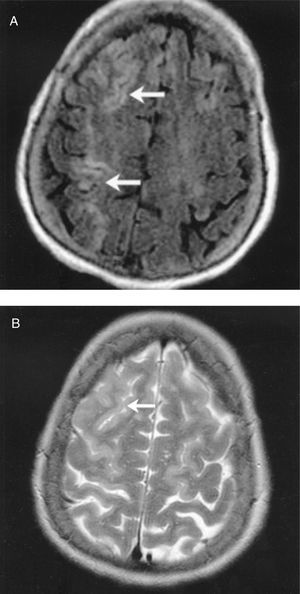

En las primeras 48 h, se realizó un primer estudio de neuroimagen con TC craneal en 50 pacientes. Sólo un estudio mostró hemorragia cerebral, a pesar del potencial riesgo que todos los pacientes sufren por precisar anticoagulación a dosis altas durante el procedimiento quirúrgico y la coagulopatía secundaria al uso de un circuito extracorpóreo. Destaca que, en este estudio inicial, en 35 (70%) pacientes no se observaron hallazgos relevantes que pudieran justificar la clínica. De éstos, en 23 pacientes persistió la clínica neurológica más de 24 h y se realizó un segundo estudio de control para buscar posibles lesiones isquémicas (a los 7-10 días, bien en UCI o planta de hospitalización): 5 estudios demostraron regiones isquémicas coherentes con la clínica; en los 18 restantes, la TC no presentó hallazgos, por lo que también se realizó una RMC. De este último grupo de pacientes, 11 presentaron déficit motor focal; en todos los pacientes, excepto en uno (que clínicamente sólo presentó una disfasia mixta transitoria), en la RMC encontramos áreas de infarto agudo o subagudo en diferentes localizaciones, fundamentalmente de pequeño tamaño, en distribución periférica, en territorios frontera, que podrían justificar los hallazgos clínicos (tabla 1). Estas imágenes aparecen hiperintensas en las imágenes de las secuencias T2 y secuencia FLAIR (secuencia de supresión de líquido cefalorraquídeo). También se realizó RMC en 4 pacientes con encefalopatía leve-moderada y sin hallazgos radiológicos en la TC; de éstos, 1 estudio no mostró alteraciones significativas, pero en los otros 3 se observaron lesiones similares a las descritas previamente en los pacientes con ictus, mostrando lesiones hiperintensas sugerentes de infartos agudos o subagudos. Por último, se realizó RMC en 3 pacientes con una clínica de encefalopatía severa y coma superior a 48 h; en ellos se objetivaron áreas múltiples de infarto a nivel cortical, que aparecieron como una hiperintensidad cortical global, con edema en las circunvoluciones. En las figuras 3 y 4 se presentan ejemplos de RMC en ictus posquirúrgicos, con TC de cráneo sin hallazgos patológicos. En la figura 5 se observa la RMC de un paciente con despertar prolongado y posterior afectación del nivel de conciencia durante aproximadamente 36 h y TC craneal sin hallazgos.

Fig. 3. Paciente sometido a sustitución valvular aórtica. Hemiparesia izquierda y disminución del nivel de conciencia. Dos tomografías computarizadas craneales sin hallazgos. En la resonancia magnética cerebral se observa una lesión hiperintensa en región frontoparietal derecha en las secuencias T2 y FLAIR.